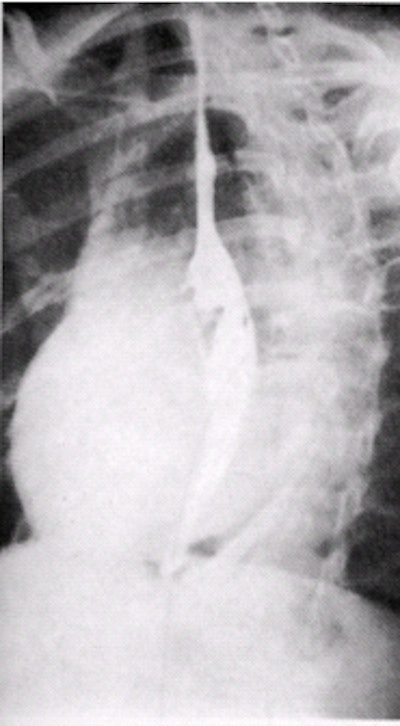

| Single-contrast study of esophagus in RAO position with table top in head-down -20° position. Image courtesy of Dr. Naveed Ahmad. |

Table-top position: the table is declined to -20° to allow for a full esophageal distension

- Place the patient in the right anterior oblique (RAO) position to offset the esophagus from the spine. The patient’s right arm is placed alongside the body, with the left knee flexed.

- The technologist will ask the patient to continuously drink the barium. This fills and distends the esophagus while the technologist obtains images of the proximal esophagus, midesophagus, and the distal esophagus, including an open lower esophageal sphincter (magnified if possible).